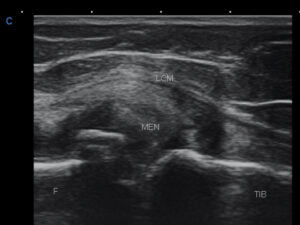

Modificari meniscale importante (genunchi)